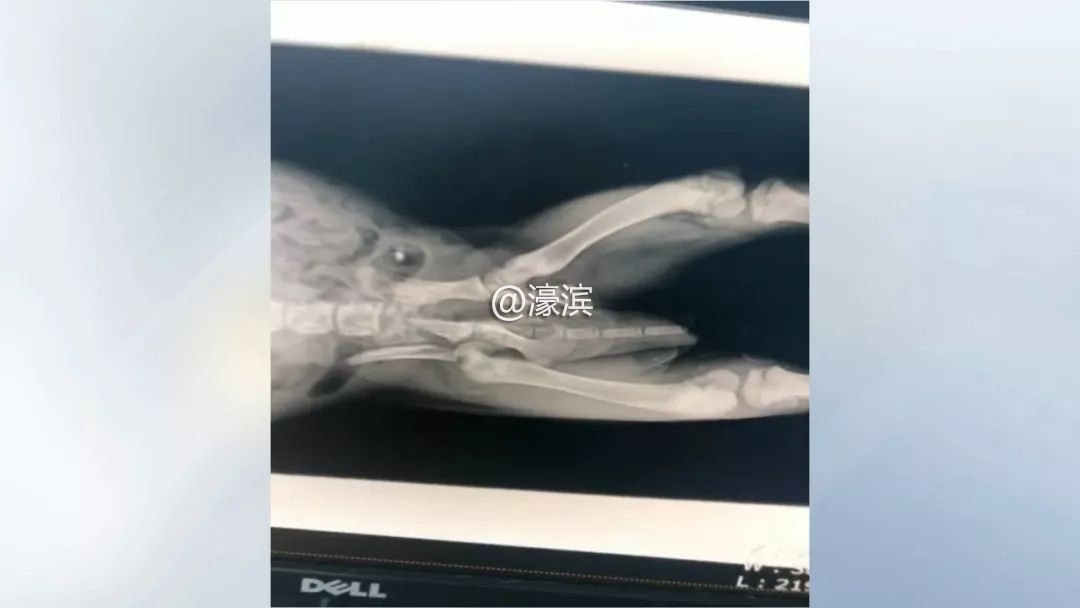

宠物医院负责人 袁嘉:送过来之后检查发现整个盆骨粉碎性骨折,再加上股骨头的断裂,再加上腹腔和胸腔的大面积的内出血。

确诊伤情后,兽医们立即为小狗进行手术。惋惜的是,由于受伤太重,经过大家三个小时的努力,最终还是没能抢救过来。

宠物医院负责人 袁嘉:当我们剖腹探查之后发现,它是肾脏破裂,这就没有办法了,我们大家都已经尽力了。